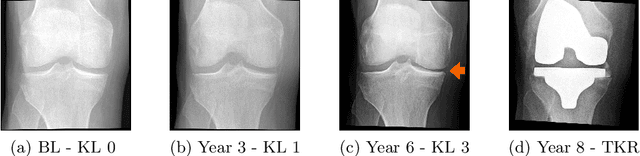

Abstract:Knee Osteoarthritis (KOA) is a highly prevalent chronic musculoskeletal condition with no currently available treatment. The manifestation of KOA is heterogeneous and prediction of its progression is challenging. Current literature suggests that the use of multi-modal data and advanced modeling methods, such as the ones based on Deep Learning, has promise in tackling this challenge. To date, however, the evidence on the efficacy of this approach is limited. In this study, we leveraged recent advances in Deep Learning and, using a Transformer approach, developed a unified framework for the multi-modal fusion of knee imaging data. Subsequently, we analyzed its performance across a range of scenarios by investigating multiple progression horizons -- from short-term to long-term. We report our findings using a large cohort (n=2421-3967) derived from the Osteoarthritis Initiative dataset. We show that structural knee MRI allows identifying radiographic KOA progressors on par with multi-modal fusion approaches, achieving an area under the ROC curve (ROC AUC) of 0.70-0.76 and Average Precision (AP) of 0.15-0.54 in 2-8 year horizons. Progression within 1 year was better predicted with a multi-modal method using X-ray, structural, and compositional MR images -- ROC AUC of 0.76(0.04), AP of 0.13(0.04) -- or via clinical data. Our follow-up analysis generally shows that prediction from the imaging data is more accurate for post-traumatic subjects, and we further investigate which subject subgroups may benefit the most. The present study provides novel insights into multi-modal imaging of KOA and brings a unified data-driven framework for studying its progression in an end-to-end manner, providing new tools for the design of more efficient clinical trials. The source code of our framework and the pre-trained models are made publicly available.